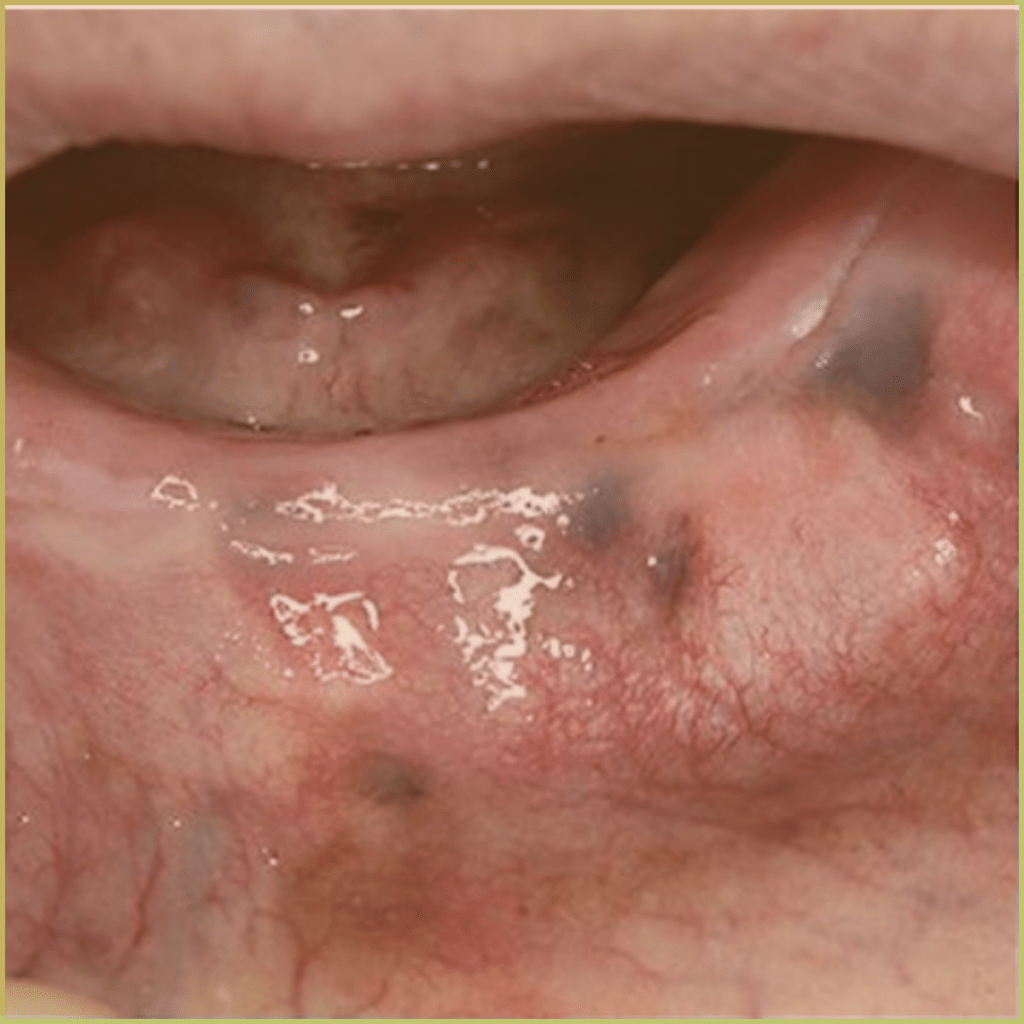

AMALGAM TATTOO

Amalgam Tattoo refers to the discoloration seen in oral tissues where dental amalgam has been deposited. The common clinical presentation includes:

- Well differentiated gray, blue or black focal macule.

- Asymptomatic lesions with no indication of associated inflammation.

Diagnosis is based on the lesion history, clinical presentation, and radiographic analysis only. If biopsied, microscopic findings may include:

- Fragments of metal within connective tissue.

- Metal staining of reticulin fibers.

- Particles may be surrounded by fibrous tissue.

- Granulomatous inflammation with a mixture of lymphocytes and plasma cells.